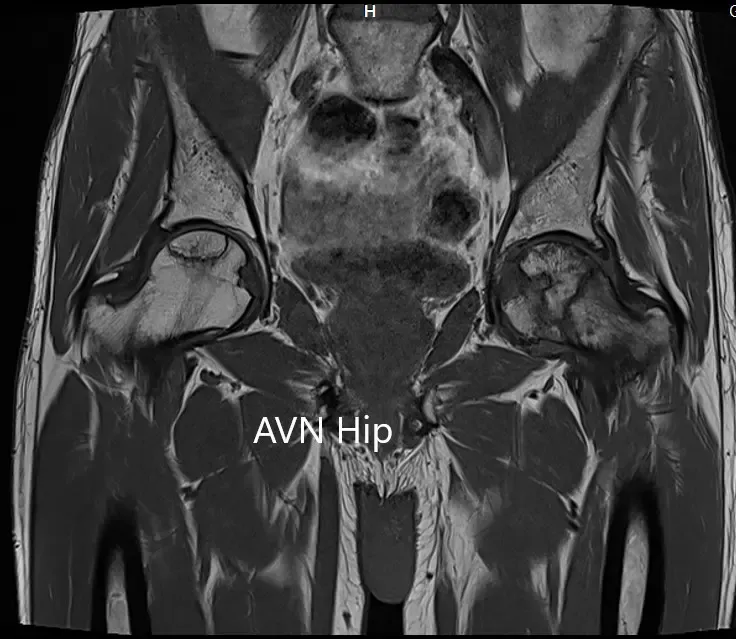

La cabeza femoral izquierda estaba colapsada con contorno irregular y muestra áreas de intensidad de señal alterada con una línea de demarcación. Zonas hipointensas tanto en T1WI como T2WI observadas en la cabeza sugestivas de esclerosis. Se observa edema de médula circundante. Una pequeña cantidad de derrame articular con pocos osteófitos observados. Se conservó el espacio de la articulación.

La cabeza femoral derecha muestra áreas de intensidad de señal alterada con la línea de demarcación serpiginosa visualizada; áreas hipointensas tanto en T1WI como T2WI se observan en la cabeza que sugieren esclerosis. El contorno femoral de la cabeza era normal. Se observa edema de médula circundante. Se observa un pequeño derrame articular. Se preserva el espacio articular.

El porcentaje de áreas necróticas en cabezas femorales bilaterales es aproximadamente del 60-70%.

Sección coronal T1WI de la resonancia magnética que muestra AVN en cadera.

Sección coronal T2WI de la resonancia magnética que muestra AVN de cadera.